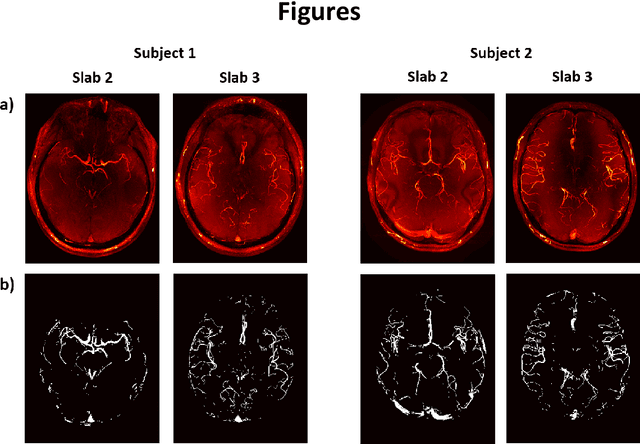

Abstract:Purpose: 3D Time-of-flight (TOF) MR Angiography (MRA) can accurately visualize the intracranial vasculature, but is limited by long acquisition times. Compressed sensing (CS) reconstruction can be used to substantially accelerate acquisitions. The quality of those reconstructions depends on the undersampling patterns used in the acquisitions. In this work, optimized sets of undersampling parameters using various acceleration factors for Cartesian 3D TOF-MRA are established. Methods: Fully-sampled datasets acquired at 7T were retrospectively undersampled using variable-density Poisson-disk sampling with various autocalibration region sizes, polynomial orders, and acceleration factors. The accuracy of reconstructions from the different undersampled datasets was assessed using the vessel-masked structural similarity index. Results were compared for four imaging volumes, acquired from two different subjects. Optimized undersampling parameters were validated using additional prospectively undersampled datasets. Results: For all acceleration factors, using a fully-sampled calibration area of 12x12 k-space lines and a polynomial order of around 2-2.4 resulted in the highest image quality. The importance of sampling parameter optimization was found to increase for higher acceleration factors. The results were consistent across resolutions and regions of interest with vessels of varying sizes and tortuosity. In prospectively undersampled acquisitions, using optimized undersampling parameters resulted in a 7.2% increase in the number of visible small vessels at R = 7.2. Conclusion: The image quality of CS TOF-MRA can be improved by appropriate choice of undersampling parameters. The optimized sets of parameters are independent of the acceleration factor.